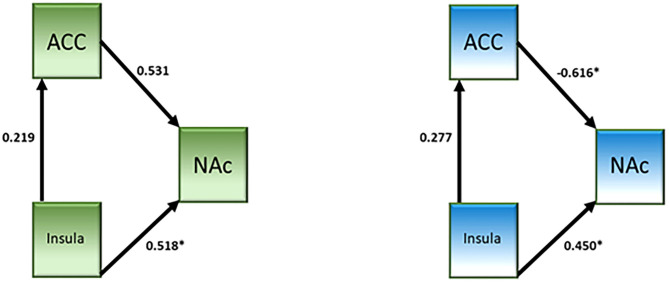

A network analysis was performed. The unconstrained model had a good fit (χ2 = 0.64, p = 0.42, CFI = 1.000, IFI = 1.019). Both groups showed a significant connection from the insula to NAc (see Table 4 and Figure 3). Neither group showed a significant connection from the insula to the dACC. The connection from the dACC to the NAc was found to be significant for the non-user group but not the CB user group. When directly comparing the parameter estimates, the connection from the dACC to the NAc was found to be significantly different between groups [z-score = −3.121, p < 0.05]. Additionally, the connectivity from the dACC to the NAc was negative in the non-user group, suggesting that the dACC has an inhibitory effect on the NAc in non-CB users but not CB users.

Table 4: Effective connectivity parameter estimates.

| Estimate | S.E. | C.R. | p | |||

|---|---|---|---|---|---|---|

| CB users | ||||||

| dACC | < — | Insula | 0.219 | 0.176 | 1.248 | 0.212 |

| NAC | < — | Insula | 0.518 | 0.228 | 2.271 | 0.023 |

| NAC | < — | dACC | 0.531 | 0.311 | 1.708 | 0.088 |

| Non-users | ||||||

| dACC | < — | Insula | 0.277 | 0.234 | 1.186 | 0.236 |

| NAC | < — | Insula | 0.45 | 0.175 | 2.579 | 0.01 |

| NAC | < — | dACC | −0.616 | 0.196 | −3.14 | 0.002 |

The primary goal of the current study was to explore the hypothesis that CB interacts with the brain network responsible for risky decision making. The results show that in the group of high functioning chronic CB users the effect is minimal in that there were no fMRI-measured brain activation differences compared to non-using controls when performing the BART task. While there were no brain activation differences between groups, effective connectivity analysis revealed significantly attenuated connectivity between the dACC to the NAc in CB users compared to controls. The results may also suggest that CB users may be more risk averse than non-using controls.

The connectivity from the dACC to the NAc was attenuated in CB users; this attenuation was linked to risky decision-making processes as it was observed for the risk parametric modulator. In addition the connectivity was inhibitory in non-users but not in CB users. A study by Lichentstein et al. (ref. 18) showed increased functional connectivity between the NAc and dACC in CB users in response to cannabis-related cues relative to neutral cues. The differences between the Lichentstein et al. study and the current study may account for the differences in results, namely the task and the stimuli (money vs. cannabis). However, both studies show that the connectivity between the dACC and NAc are impacted by chronic CB use. The core of the NAc has been shown to be anatomically connected to the dACC (ref. 40). Phasic dopamine release in the core, but not the shell, has been observed following reward-predictive cues (ref. 41) and that dopamine release is related to the subjective reward value of the cue (ref. 42–ref. 44). This suggests that the subjective value of the reward plays a role in how individuals make decisions regarding said rewards, which may account for group differences observed in the current study as well as previous studies showing differences in reward processing as a function of the reward in CB users. Additionally, it may be salience of loss that drives the behavior of CB users, like was seen in Wesley et al. (ref. 14). It will be important in future studies to assess the subjective reward value in participants in order to more fully understand risky decision-making and reward processing.

This preliminary study examining risky decision-making suggests, while minimal, that CB use is associated with functional connectivity from the dACC to the NAc. The decrease in connectivity and the switch between inhibitory to excitatory connectivity may suggest the use of different strategies, or differences in the subjective value of the reward between groups. Further research is necessary to disentangle these possibilities and to replicate the current findings.